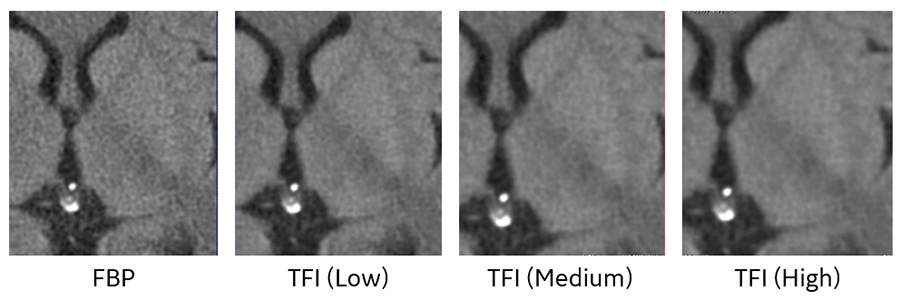

TFI再構成は、そのノイズ低減度合いを『Low』、『Medium』、『High』の3つのレベルから選択可能です。当院では頭部領域は淡いコントラストにおける境界の視認性を高めるために少しノイズを残した『Low』、その他体幹部などは『Medium』を使用しています。

Fig.5 再構成法によるノイズ低減度合いの違い